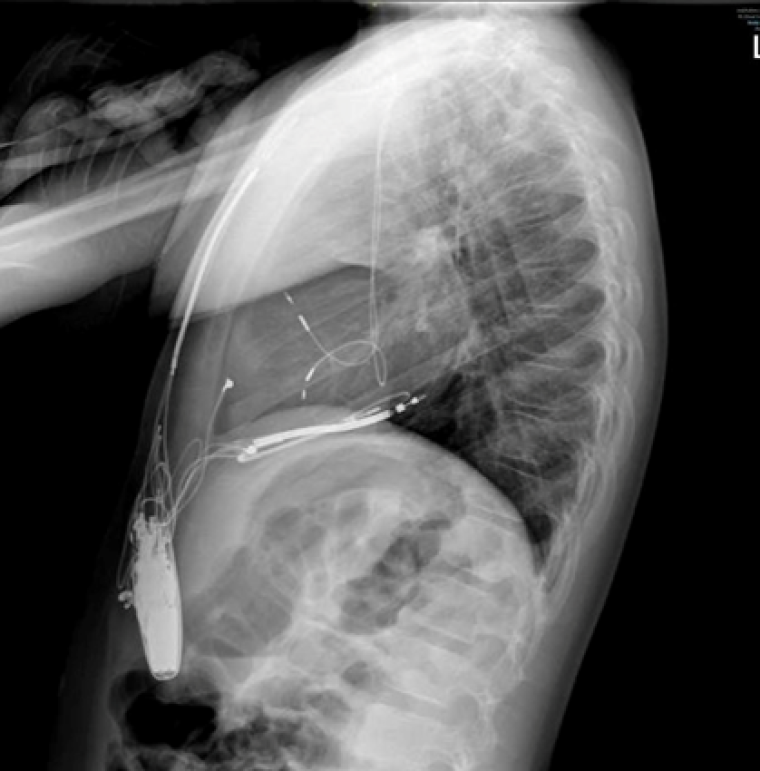

During the procedure, VF was induced with burst pacing after administering Isoprenaline. Despite adjusting the sensing threshold to 0.6mV, the ICD could not effectively detect VF, and a successful shock required changing the configuration from coil to can. Recognizing the device's inability to safely provide effective therapy during VF, a multi-disciplinary team meeting approved a "hybrid approach". The patient underwent ICD system revision, with the generator changed and left in an abdominal position. A transvenous atrial and ventricular pace-sense lead was inserted and tunnelled subcutaneously to the abdominal pocket, and an ICD shock coil was positioned subcutaneously anteriorly at the left parasternal site, with the shock set between the prior epicardial coil and the new subcutaneous coil (Image 3, 4a,b).